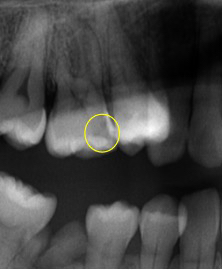

龋坏牙X线片

邻牙已龋坏